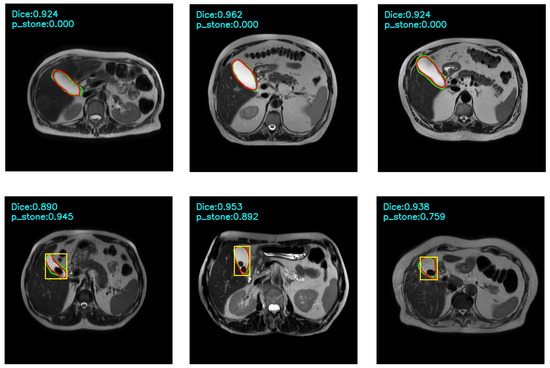

A Deep Learning-Based Decision Support System for Cholelithiasis in MRI Data

Background: Cholelithiasis can lead to significant complications if not diagnosed and treated promptly. Recent advances in deep learning and the improved ability of computer systems to detect clinically significant textural and morphological patterns in magnetic resonance imaging (MRI) can help reduce the time [...] Read more.

Background: Cholelithiasis can lead to significant complications if not diagnosed and treated promptly. Recent advances in deep learning and the improved ability of computer systems to detect clinically significant textural and morphological patterns in magnetic resonance imaging (MRI) can help reduce the time and resources required for the radiological evaluation of the gallbladder and cholelithiasis. Objective: To detect cholelithiasis, a support system with a graphical user interface for magnetic resonance (MR) images of the gallbladder was implemented to reduce the manual effort and time required to identify gallstones. Method: A commonly used deep learning model for pixel-level mask generation and instance segmentation, Mask Region Based Convolutional Neural Network (Mask R-CNN), was modified, trained, and evaluated to provide a robust pipeline for automated analysis. The primary aim was to automatically locate and label the gallbladder in T2-weighted axial MR images to detect gallstones and highlight the visual characteristics of the target region, thereby supporting radiologists. All automation was designed to operate on a single optimal slice instead of the entire volume. While this approach limits generalisability, it offers a practical starting point for method development. This setup reflects a feasibility-oriented design, rather than a comprehensive diagnostic capability. The dataset included 788 axial MR images from different patients. Each image was labeled and segmented by an experienced radiologist to train and test the models at the image level. Results: The proposed model with squeeze and excitation (SE) modification improved classification accuracy, and at the image level, stone detection improved in terms of accuracy, precision, and specificity, although recall and F1 scores slightly decreased. Conclusions: The results show that the modified Mask R-CNN model can detect gallstones with up to 0.89 accuracy, supporting the clinical applicability of the proposed method. Full article